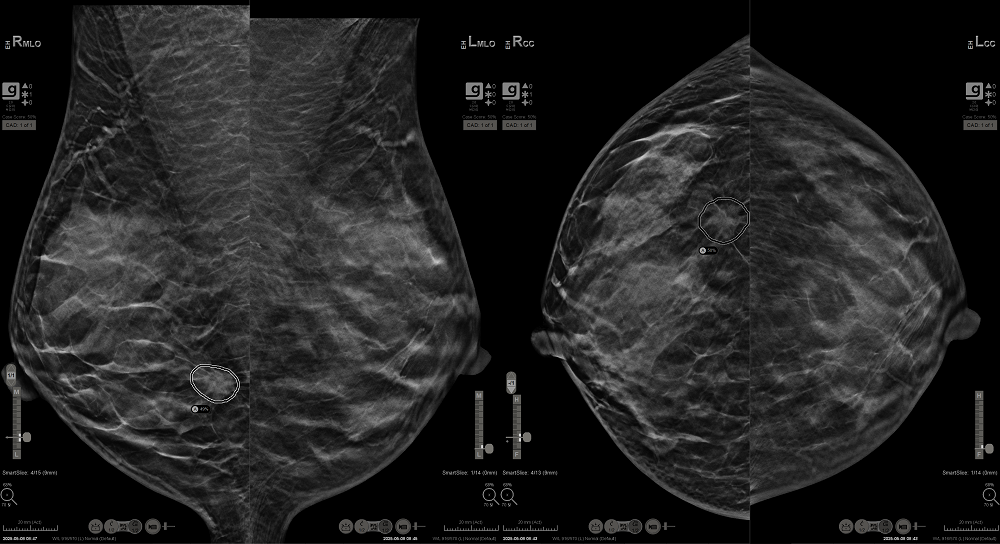

고려대학교 구로병원 영상의학과에서 진행된 유방 촬영 장비 신제품 테스트 중 대상자에서 조기 암 의심 병변을 발견했다. 이날 촬영은 병원 내에서 환자가 아닌 일반인을 대상으로 한 내부 테스트의 일환으로 진행되었으며, 촬영 대상자 중 한 명인 A 직원의 오른쪽 유방 영상에서 이상 소견이 포착되었다. 당시 촬영은 최신 AI 진단 보조 솔루션이 적용된 장비로 진행되었다.

영상 판독을 맡은 김수연 고대구로병원 영상의학과 교수는 “A직원에서 발견된 유방암은 무증상이었고, 석회화 없이 비 대칭 음영으로만 나타났으며, 크기가 작은 초기 단계였고 치밀 유방이어서 유방 촬영술에서 명확한 식별이 어려운 케이스였다. 그러나 AI는 해당 부위를 정확히 강조하였고, 이로 인해 판독 과정에서 해당 부위를 더욱 주의 깊게 관찰하게 되었으며, 그 결과 실제로 의심 소견을 포착할 수 있었다”고 말했다.

홀로직 코리아가 출시한 인공지능 기반 유방암 진단 보조 솔루션 ‘Genius AI Detection 2.0’은 홀로직의 3D 유방촬영장비와 연동되어 동작하는 AI 솔루션으로, 3D 이미지를 기반으로 병변의 위치를 시각적으로 강조해 방사선 전문의의 판독을 보조한다. 해당 기술은 94%의 민감도로 유방암 의심 병변을 탐지하며, 최근 미국에서 7500건 이상의 임상 데이터를 통해 다인종, 다양한 연령층에 걸쳐 데이터를 입증했다.